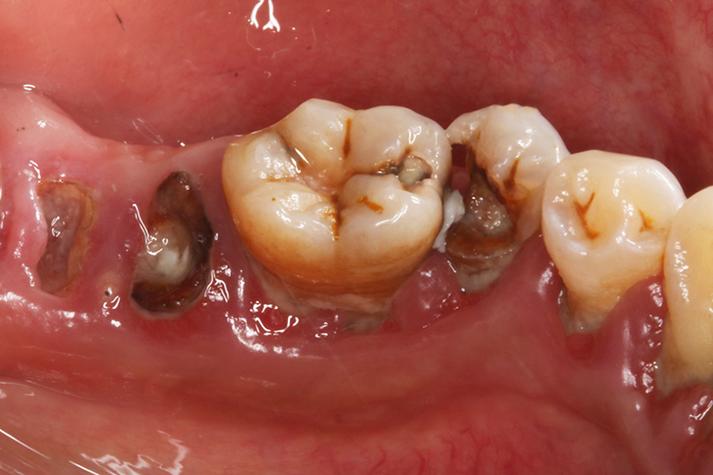

中期/深龋(形成明显蛀洞)

如果早期没有处理,细菌会继续腐蚀,穿透牙釉质,到达更软的牙本质层,这时,一个真正的“洞”就形成了。

- 明显的黑洞或棕色/褐色小洞: 这是我们最常说的“虫牙”,牙齿上出现了一个看得见的、有深度的洞。

- 边缘粗糙不齐: 蛀洞的边缘通常不是平滑的,而是参差不齐的。

- 食物残渣堆积: 这个小洞很容易塞住食物,你可能会在刷牙或用牙线时发现。

简单说: 牙齿上有个明显的黑洞,吃冷热酸甜会疼,吃东西容易塞牙。